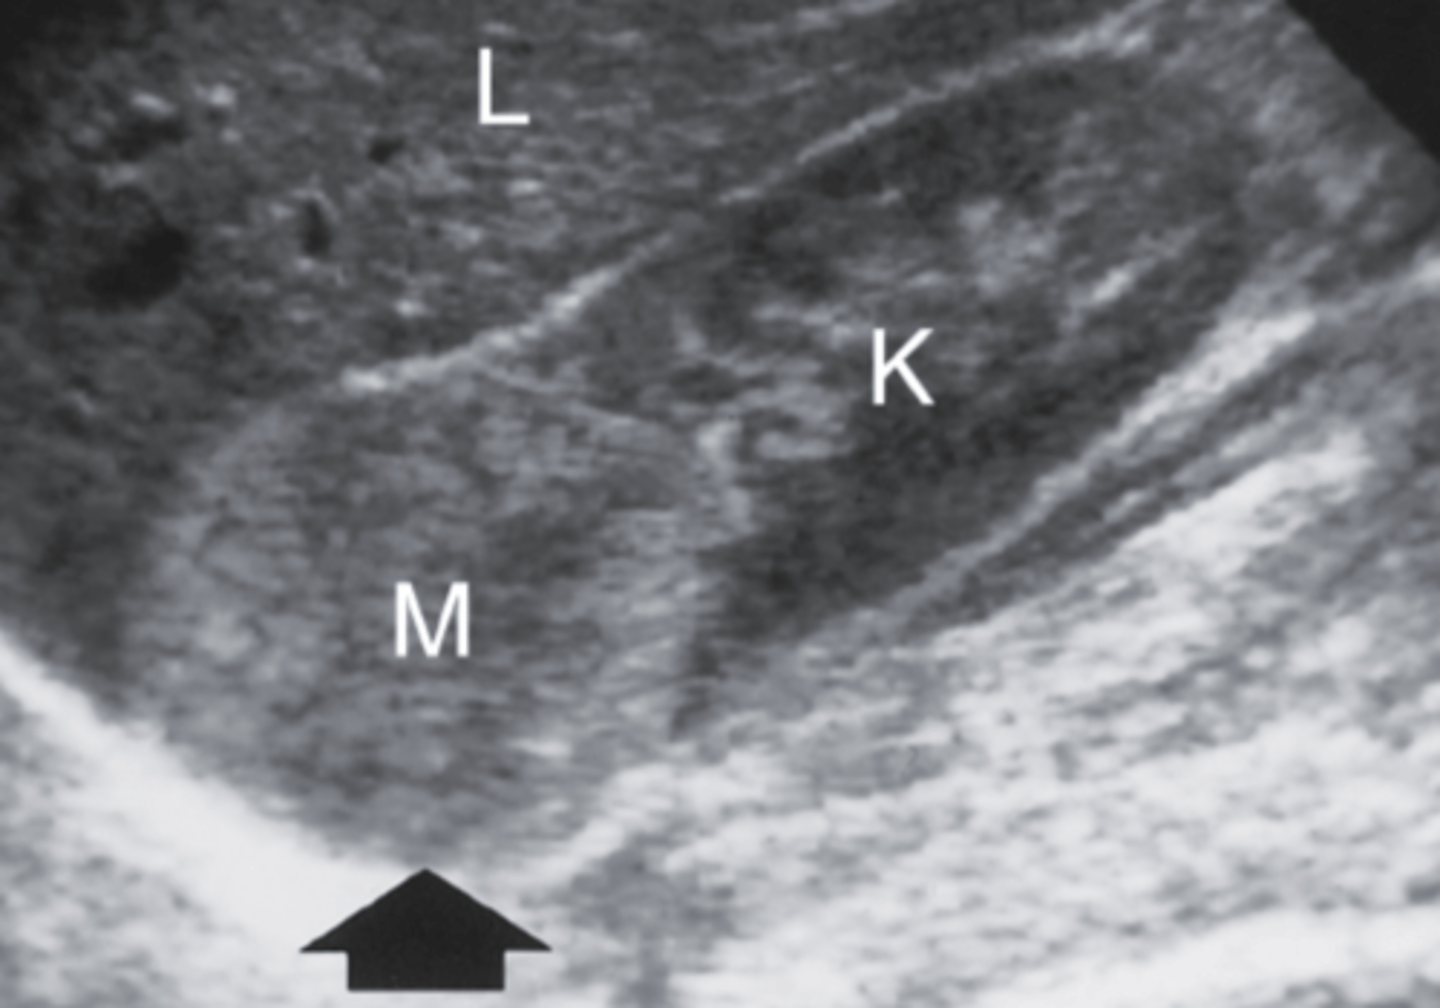

4. What is the arrow in Figure 7-41 most likely identifying in this asymptomatic patient?

a. Hypernephroma

b. Nephroblastoma

c. Renal hemangioma

d. Angiomyolipoma